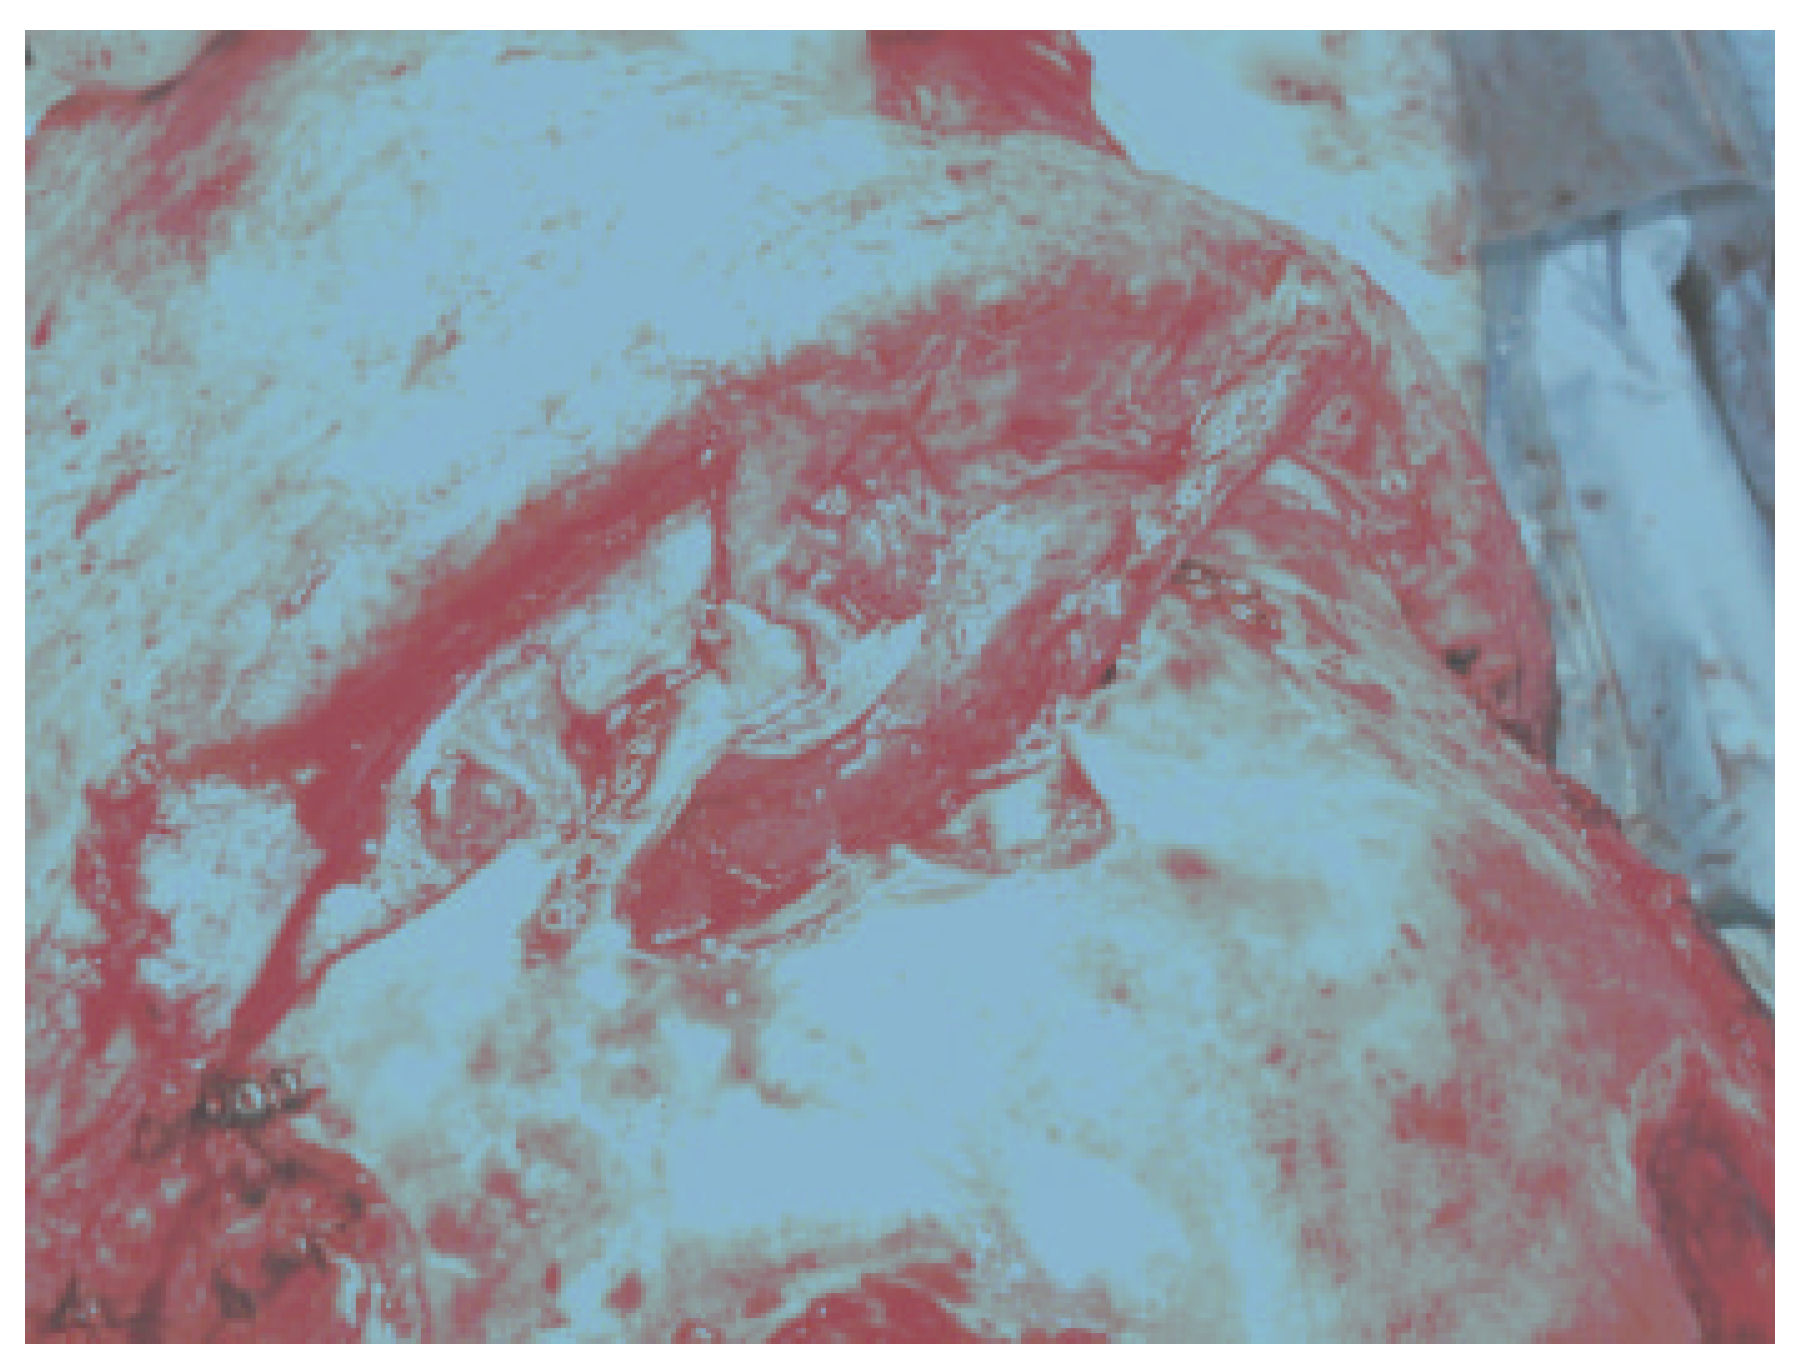

Figure 3.

Placement of a well-vascularized pericranial flap for separation of the anterior skull base from the nasal cavity. The ducts are plugged with temporalis muscle after thorough mucosal removal, and the pericranial flap is tucked in and secured with fibrin glue.